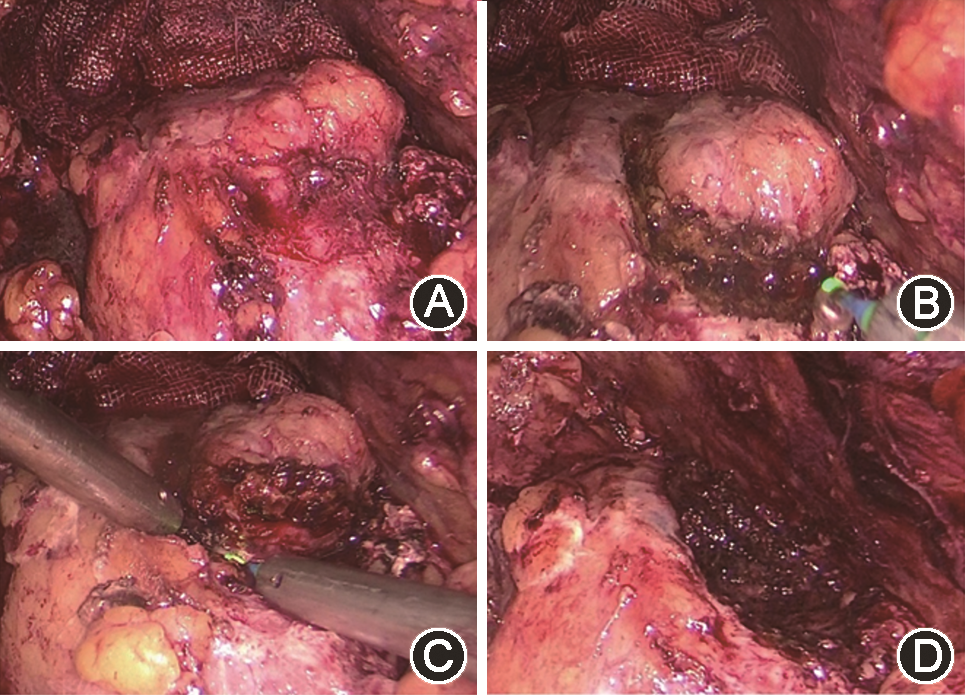

光纤500 μm,能量设置25~37.5 W,从肿瘤边缘5 mm的正常肾组织切开肾被膜,一直暴露至肾肿瘤假包膜,同时另一个操作孔使用吸引器进行钝性分离,寻找肿瘤包膜,然后沿着肿瘤包膜完整切除肿瘤。边切割边进行止血处理,肿瘤切除后仔细观察创面有无活动性出血,使用铥激光彻底止血。沿肋缘下将操作孔打开,将肾脏肿瘤完整取出(图2)。术野放置引流管腋前线伤口引出。

沿着肾被膜充分显露肿瘤;B:沿肿瘤边缘切开正常肾实质至肿瘤包膜;C:钝性分离沿肿瘤包膜完整切除肿瘤;D:切除后创面